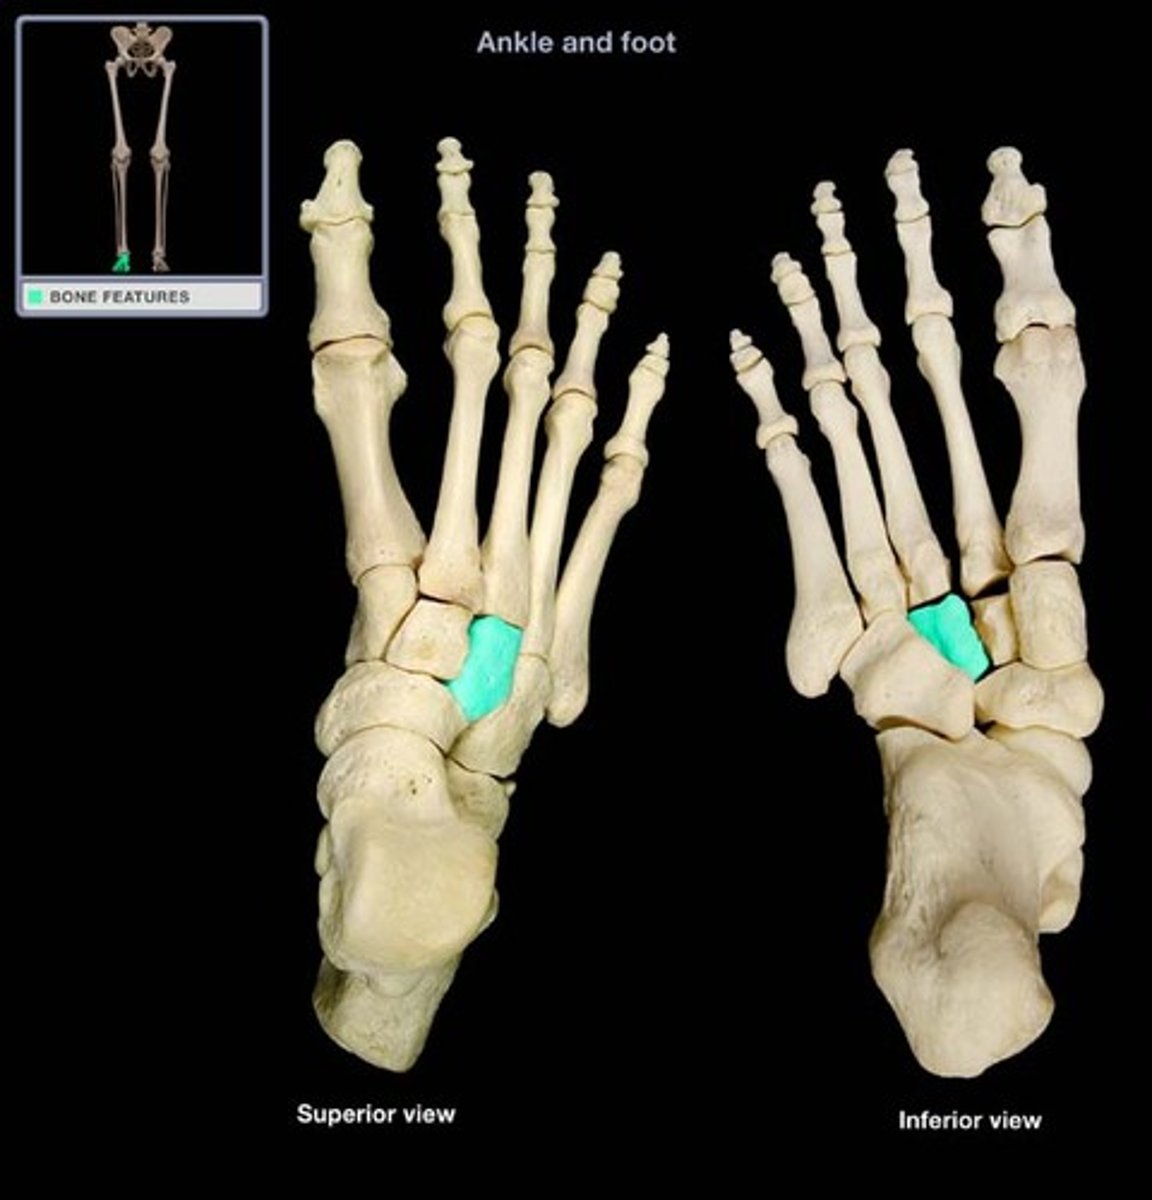

Lateral cuneiform